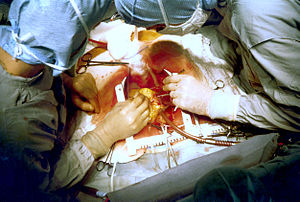

Coronary artery bypass surgery

Despite the guidelines, emergency bypass surgery for the treatment of an acute myocardial infarction (MI) is less common then PCI or medical management. In an analysis of patients in the U.S. National Registry of Myocardial Infarction (NRMI) from January 1995 to May 2004, the percentage of patients with cardiogenic shock treated with primary PCI rose from 27.4% to 54.4%, while the increase in CABG treatment was only from 2.1% to 3.2%.

Emergency coronary artery bypass graft surgery (CABG) is usually undertaken to simultaneously treat a mechanical complication, such as a ruptured papillary muscle, or a ventricular septal defect, with ensueing cardiogenic shock. In uncomplicated MI, the mortality rate can be high when the surgery is performed immediately following the infarction. If this option is entertained, the patient should be stabilized prior to surgery, with supportive interventions such as the use of an intra-aortic balloon pump. In patients developing cardiogenic shock after a myocardial infarction, both PCI and CABG are satisfactory treatment options, with similar survival rates.

Coronary artery bypass surgery involves an artery or vein from the patient being implanted to bypass narrowings or occlusions on the coronary arteries. Several arteries and veins can be used, however internal mammary artery grafts have demonstrated significantly better long-term patency rates than great saphenous vein grafts. In patients with two or more coronary arteries affected, bypass surgery is associated with higher long-term survival rates compared to percutaneous interventions. In patients with single vessel disease, surgery is comparably safe and effective, and may be a treatment option in selected cases. Bypass surgery has higher costs initially, but becomes cost-effective in the long term. A surgical bypass graft is more invasive initially but bears less risk of recurrent procedures (but these may be again minimally invasive).